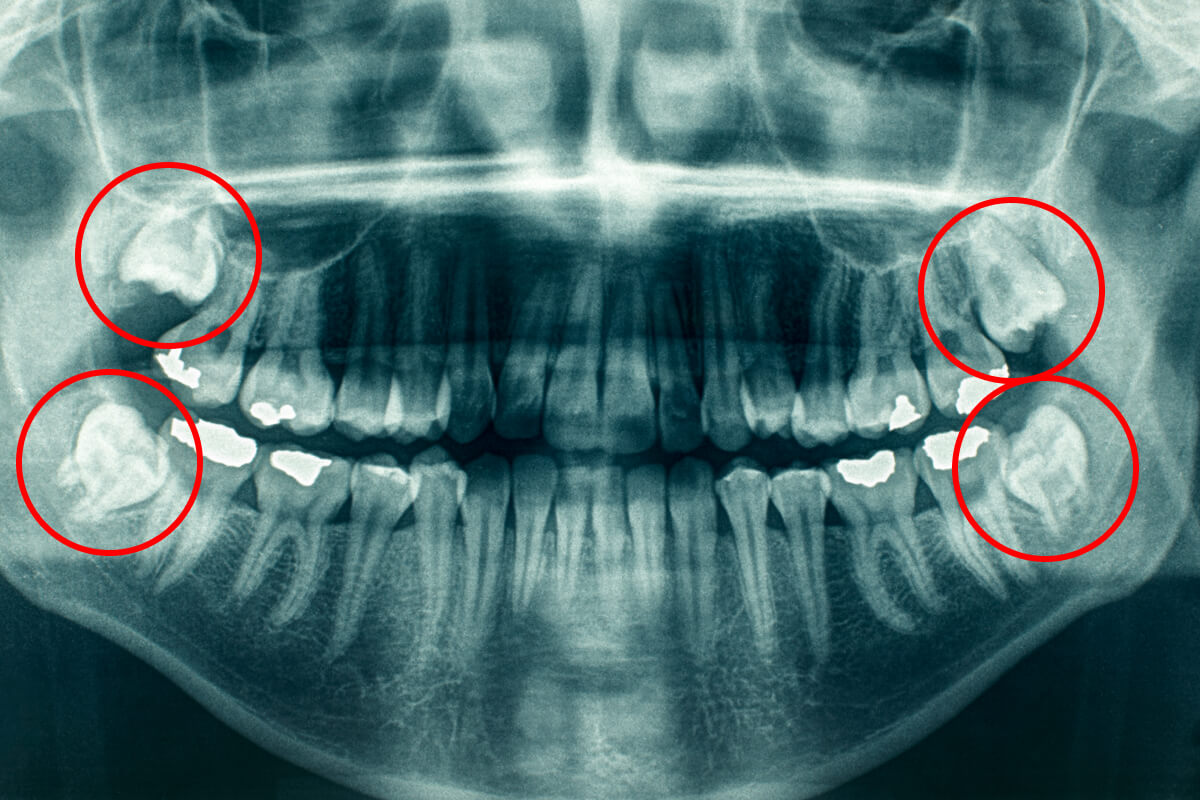

2. Problémové zuby múdrosti

Ak spôsobujú bolesť, tlačia na ostatné zuby alebo vyvolávajú opakované zápaly.

Extrakcia zuba múdrosti | Dental Centrum NIVY